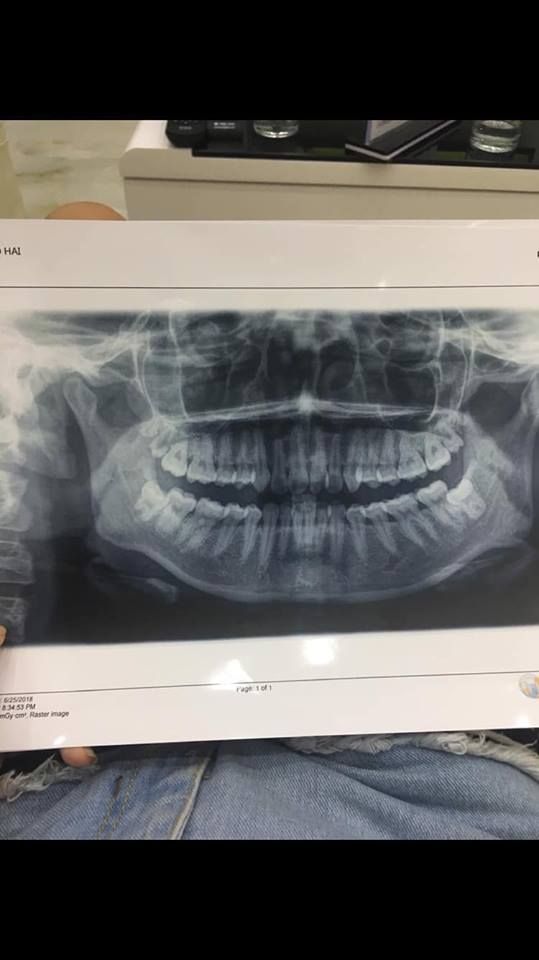

Thu Thảo (25 tuổi) vừa trải qua quá trình niềng răng hô, khấp khểnh tại nha khoa Thuỳ Anh. Thời gian điều trị kéo dài trong 3 năm, nếm đủ những khó khăn vất vả nhưng thành quả mà Thảo nhận được lại vô cùng xứng đáng.